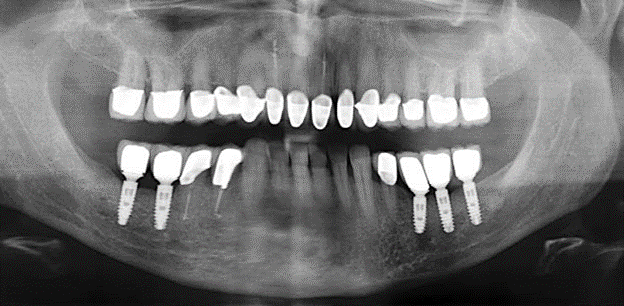

Eine 52-jährige Patientin stellte sich nach Zahnverlust im 3. Quadranten erstmals 2004 vor. Sie hatte den Wunsch nach einer prothetischen Neuversorgung. Im Rahmen der parodontologischen und radiologischen Diagnostik zeigte sich ein ausgeprägter parodontologischer Behandlungsbedarf. Die Zähne 48, 28, 27 zeigten zudem eine infauste Prognose und wurden entfernt (Abb. 1). Nach der erfolgreich abgeschlossenen systematischen PARTherapie wurde eine festsitzende implantatprothetische Versorgung mit Insertion von fünf Implantaten in Regio 35, 36, 37 und 46, 47 durchgeführt. Die prothetische Versorgung der natürlichen Zähne erfolgte mit verblendeten Zirkonoxidkeramikkronen, die Implantate wurden mit zweiteiligen individuellen Zirkonoxidabutments und ebenfalls verblendeten Kronen aus einer Zirkonoxidkeramik versorgt (Cercon base colored, Dentsply Sirona Lab). Die definitive Insertion der prothetischen Versorgung erfolgte im Jahr 2005.

Im Rahmen der ZehnJahresKontrolle zeigten sich keine Hinweise auf einen fortschreitenden parodontalen Attachmentverlust oder einen periimplantären Knochenverlust (Abb. 3).

Für den klinischen Langzeiterfolg des parodontal kompromittierten Patienten ist die standardisierte und regelmäßige risikoadaptierte Betreuung im Rahmen der UPT der zentrale Baustein des Behandlungserfolgs. Dies gilt in besonderer Weise für Patienten, die nach erfolgreich abgeschlossener parodontaler Sanierung mit Implantaten versorgt wurden (Abb. 11a und b).